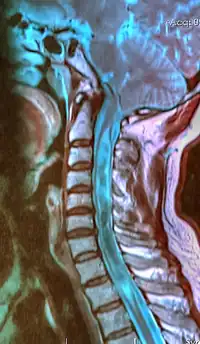

| A sagittal FLAIR MRI scan, from a patient with an Arnold-Chiari malformation, demonstrating tonsillar herniation of 7 mm. | |